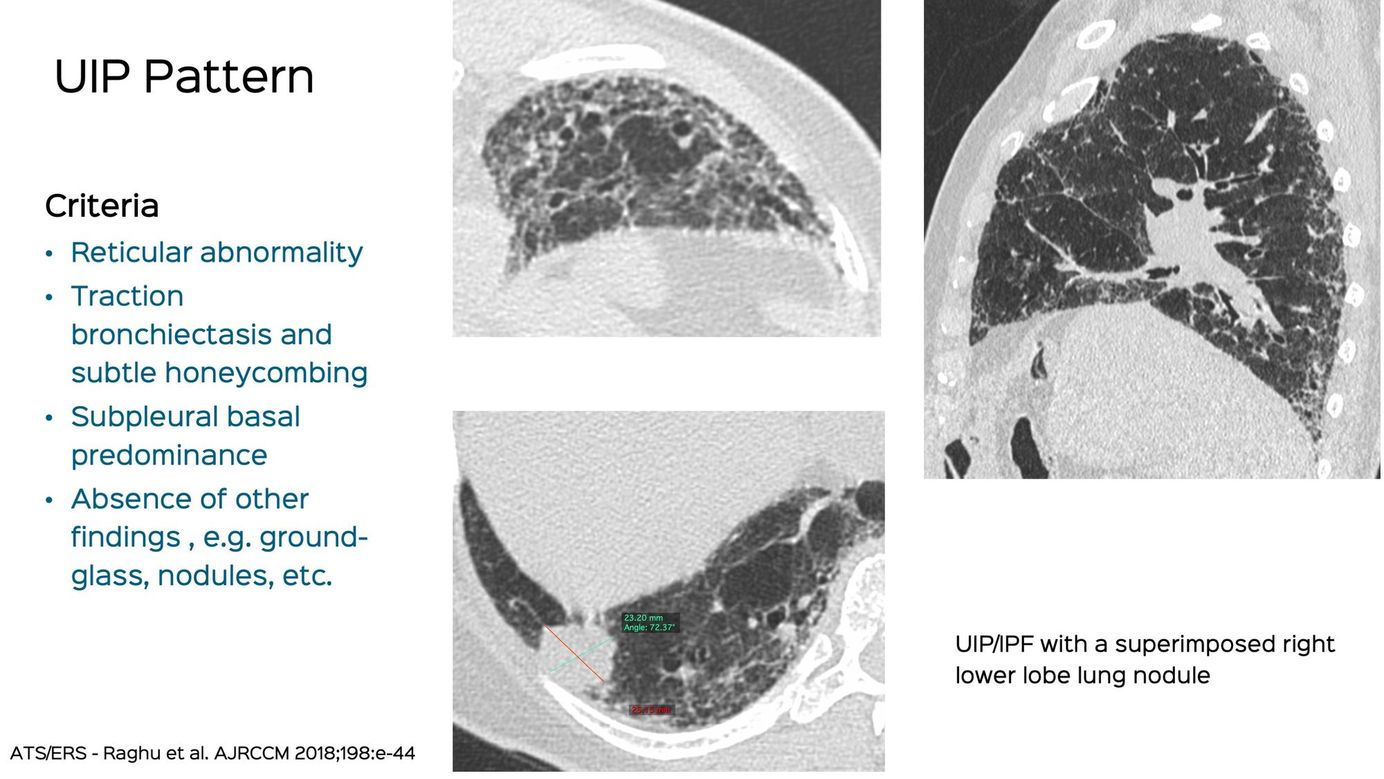

Case 7: UIP/IPF with a Superimposed Lung Complication Members Public

75-years old man with UIP IPF and a superimposed > 20 mm lung nodule that was biopsied and turned out to be squamous cell carcinoma.